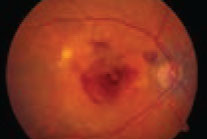

Oral eplerenone vs. PDT for CSCR

If SRF were present at the three-month follow-up, the patient would receive crossover treatment. In the primary oral eplerenone patients, 38 of 46 (82.6 percent) had persistent SRF and required crossover; 11 of 50 (22 percent) that received primary half-dose PDT required crossover. At the final follow-up visit 12 months after baseline, complete SRF resolution occurred in 38 of 39 (97.4 percent) patients with primary resolution after PDT; seven of seven in those with primary resolution after eplerenone; 30 of 35 (85.7 percent) in the eplerenone-to-PDT crossover group; and five of nine (55.5 percent) in the PDT-to-eplerenone crossover group. The researchers found no significant differences in BCVA and retinal sensitivity on microperimetry among the groups at the final visit.Due to a paucity of gold-standard evidence, consensus for treatment of chronic central serous chorioretinopathy (CSCR) remains lacking. The SPECTRA study was an open-label, multicenter, randomized controlled trial to compare the anatomic and functional efficacy and safety of primary treatment with either half-dose photodynamic therapy (PDT) or 25-mg oral eplerenone daily for a week, with or without crossover in patients with CSCR. Patients with fovea-involving subretinal fluid (SRF) persisting for more than six weeks and BCVA of 20/200 or better were randomized 1:1 to receive either half-dose PDT or oral eplerenone.

This study demonstrated the superiority of half-dose PDT in the treatment of chronic CSCR, even after eplerenone treatment. CSCR remains one of the few indications for which I use PDT as a first-line therapy. It’s reassuring to see randomized controlled trial data supporting this decision. Crossover to eplerenone in patients that had suboptimal treatment with PDT wasn’t as likely to result in resolution of SRF. We need more data to determine the best treatment for this small subset of patients.